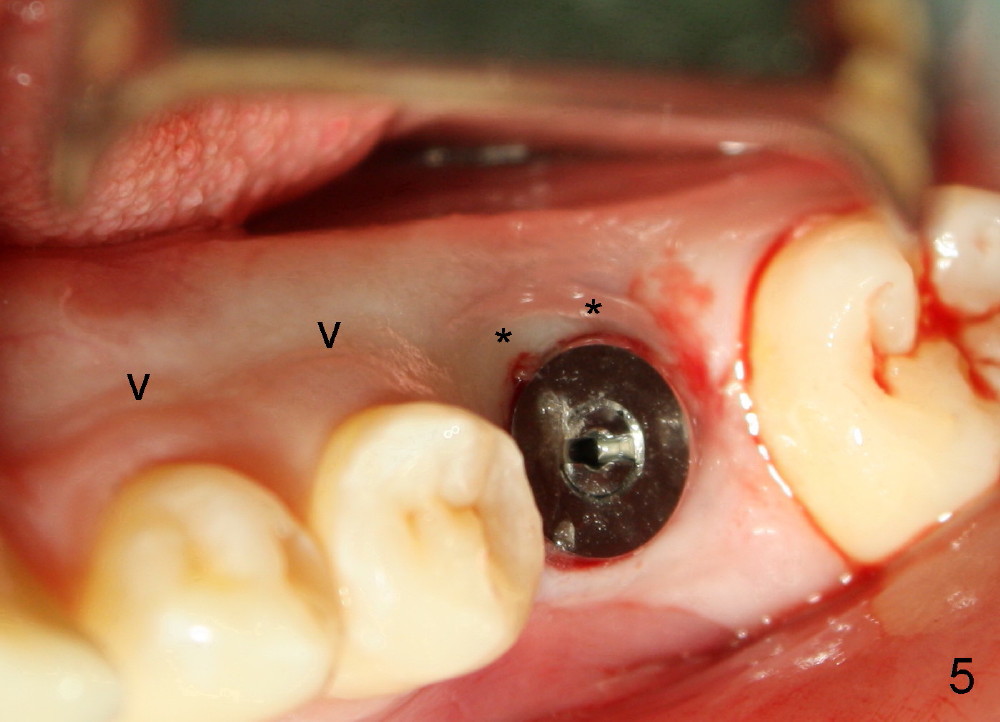

小张,男,22岁,大学刚毕业,忙于找工作,治疗不够积极,左下第一磨牙根管治疗失败,根尖,根分叉阴影(图一*),好像即刻植牙不太合适,建议拔牙后四周,六周之间回来植牙。但是他很拖拉,三个月才回来让我们看看,骨头似乎愈合不错(图二),他又消失五个月,最后还是登门,骨质仿佛继续形成(图三),植入六乘十七毫米植牙(图四,五),舌侧牙龈马上形成cuff(图五**),好像attached gingiva,与邻牙一致(箭头)。您能猜为什么植牙舌侧形成牙龈cuff?

图六是术后十天拍摄,它显示颊侧骨板明显萎缩(箭头),这可能拔牙后形成。由于颊侧骨板萎缩,植牙偏向舌侧,给舌侧牙龈施加压力,便形成牙龈cuff。